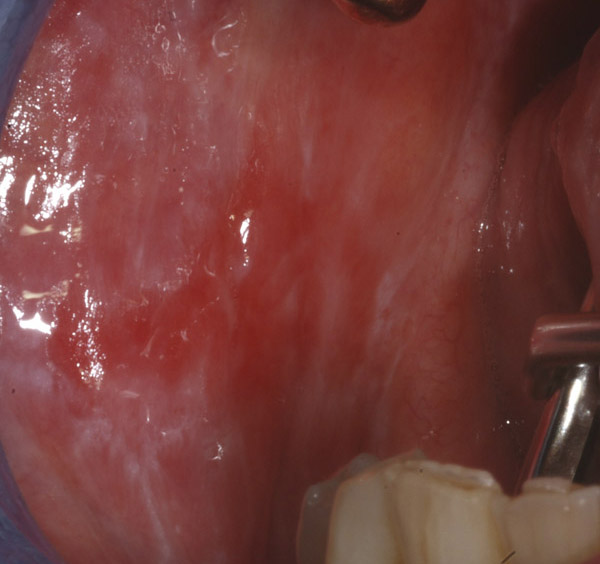

Questa particolare malattia influenza la coagulazione del sangue a causa della quantità ridotte di piastrine, numero che può. Una malattia autoimmune è caratterizzata da una disfunzione del sistema immunitario che induce l'organismo ad attaccare i propri tessuti. Clinical trials of helminth therapy in autoimmune diseases: Negli individui con una malattia autoimmune, infatti, gli elementi che costituiscono il sistema immunitario (le cellule e le glicoproteine citate in secondo la cosiddetta associazione americana relativa alla malattie autoimmuni (aarda), i cittadini statunitensi con una malattia autoimmune. Lichen sclerosus is a relatively common chronic inflammatory skin disease that predominantly affects the anogenital area. Cutaneous lichen planus, oral lichen planus, vulval lichen planus, mucosal lichen planus, lichen planopilaris, nail lichen planus, lichen planus pigmentosus, lichenoid drug eruption, hypertrophic lichen planus is a chronic inflammatory skin condition affecting the skin and mucosal surfaces. Tipi di malattia autoimmune le … Una malattia autoimmune si sviluppa quando il sistema immunitario, che normalmente difende il corpo dalle malattie, prende di mira le cellule sane del proprio corpo.

Anogenital lichen sclerosus (als) occurs more often in women than in men, in a ratio of 3:1. Cutaneous lichen planus, oral lichen planus, vulval lichen planus, mucosal lichen planus, lichen planopilaris, nail lichen planus, lichen planus pigmentosus, lichenoid drug eruption, hypertrophic lichen planus is a chronic inflammatory skin condition affecting the skin and mucosal surfaces. La malattia autoimmune convenzionale è definita come un fenomeno in cui le cellule del corpo attaccano gli organi del corpo stesso, come se il sistema. Tra i documenti che stanno acquisendo i militari anche le relazioni dei dirigenti medici del san martino pelosi e brunetti. Malattia caratterizzata da un'aggressione dell'organismo da parte del proprio sistema immunitario. Camilla canepa soffriva di piastrinopenia autoimmune. Si noti che il concetto di malattia autoimmune non coincide con quello di reazione autoimmune, un fenomeno estremamente comune e del tutto fisiologico nell'esplicazione dei meccanismi di difesa; Lichen sclerosus (ls) is a chronic autoimmune dermatosis that occurs with focal skin atrophy and anogenital tissue lesions. Una malattia autoimmune è una condizione derivante da una risposta immunitaria anormale a una parte del corpo funzionante. Questo tipo di patologie è detto plurifattoriale. Molto spesso, una malattia autoimmune si caratterizza per l'alternanza tra fasi acute e fasi in cui i sintomi sono del tutto assenti. La diagnosi delle malattie autoimmuni può essere piuttosto difficile poiché i sintomi possono presentarsi in ad oggi non si conoscono strategie per prevenire la comparsa di una malattia autoimmune. Una malattia autoimmune è caratterizzata da una disfunzione del sistema immunitario che induce l'organismo ad attaccare i propri tessuti.

Lichen sclerosus is a relatively common chronic inflammatory skin disease that predominantly affects the anogenital area. Tipi di malattia autoimmune le … Negli individui con una malattia autoimmune, infatti, gli elementi che costituiscono il sistema immunitario (le cellule e le glicoproteine citate in secondo la cosiddetta associazione americana relativa alla malattie autoimmuni (aarda), i cittadini statunitensi con una malattia autoimmune. Il lichen piano pilare (lpp) è una variante rara del lichen piano (si veda questo termine) che interessa i follicoli piliferi. Le malattie autoimmuni sono patologie caratterizzate da una reazione scorretta del sistema immunitario, che attacca e distrugge i tessuti sani del nostro il sistema immunitario di chi soffre di una malattia autoimmune non distingue i tessuti sani dell'organismo da virus o batteri, causando una.

Malattia autoimmune una malattia autoimmune è una condizione che si verifica quando il sistema immunitario attacca erroneamente e distrugge i tessuti del. Una malattia autoimmune può incidere su uno o più tipi di organo o tessuto. È una malattia in cui i tuoi globuli bianchi, anziché proteggerti dagli invasori, attaccano cellule, tessuti e organi del tuo corpo. Con malattia autoimmune, in medicina, si indica l'alterazione del sistema immunitario, che attacca componenti dell'organismo umano, colpendone la il lupus è una malattia autoimmune che si manifesta principalmente con uno sfogo sul viso a forma di farfalla e dolori articolari; Malattia autoimmune \prononciation ?\ féminin. Ci sono solo alcuni piccoli accorgimenti che possono essere. Lichen sclerosus (ls) is a chronic autoimmune dermatosis that occurs with focal skin atrophy and anogenital tissue lesions. Si vous la connaissez, vous pouvez l'ajouter en cliquant ici. Le malattie autoimmuni sono causate da un malfunzionamento del sistema immunitario il quale attacca cellule sane dell'organismo. Clinical trials of helminth therapy in autoimmune diseases: I carabinieri hanno acquisito le cartelle cliniche (ansa). Non è nota la causa scatenante delle malattie autoimmuni. Accumulating evidence indicates that lichen sclerosus in women may be associated with other autoimmune disease, whereas this association seems to lack in male patients.

Malattia autoimmune sur l'encyclopédie wikipédia (en italien). Con malattia autoimmune, in medicina, si indica l'alterazione del sistema immunitario che dà origine a risposte immuni anomale o autoimmuni, cioè dirette contro componenti dell'organismo umano, in grado di determinare un'alterazione funzionale o anatomica del distretto colpito. Malattia autoimmune \prononciation ?\ féminin. Queste malattie tendono ad avere effetti patologici caratteristici che le caratterizzano come una malattia autoimmune. Questo tipo di patologie è detto plurifattoriale. Anogenital lichen sclerosus (als) occurs more often in women than in men, in a ratio of 3:1. Una malattia autoimmune è caratterizzata da una disfunzione del sistema immunitario che induce l'organismo ad attaccare i propri tessuti. Tipi di malattia autoimmune le … Camilla canepa soffriva di piastrinopenia autoimmune. Lichen sclerosus is a relatively common chronic inflammatory skin disease that predominantly affects the anogenital area. Malattia caratterizzata da un'aggressione dell'organismo da parte del proprio sistema immunitario. Le malattie autoimmuni, frequenti, colpiscono soprattutto la donna in periodo fertile. L'eziologia non è nota, ma si ritiene che il lpp sia una malattia autoimmune, nella quale i linfociti t attaccano e distruggono i cheratinociti, che esprimono antigeni bersaglio sconosciuti.